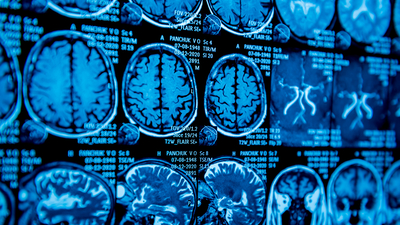

Nöroloji Uzmanı Dr. Gülten Özdemir, Parkinson’un Alzheimer’dan sonra ikinci sıklıkta görülen nörolojik bir hastalık olduğunu bilgisini paylaşarak, "Bu hastalığa 40 yaş altı kişilerde sık rastlanmaz ama son yıllarda 40 yaş altında, hatta 20'li, 30'lu yaşlarda bile Parkinson vakaları bildiriliyor" dedi.

Uzm. Dr. Özdemir, "Vücudumuzda akıcı ve koordineli hareket etmemizi sağlayan, beynin belli anatomik bölgelerinde dopamin maddesi salgılayan hücreler bulunur. Dopamin üreten bu hücrelerin dejenerasyonla kaybı sonucu dopamin üretilemez ve Parkinson hastalığı belirtileri ortaya çıkar" değerlendirmesinde bulundu.